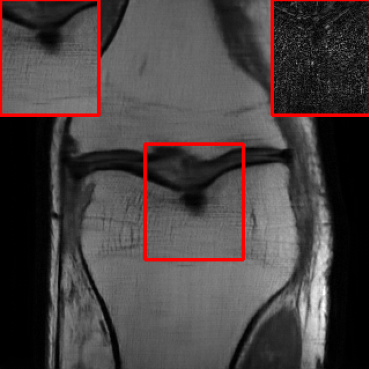

Results for the DIDN-based Reconstructor: To demonstrate adaptability to different network architectures, Table II compares reconstruction performance on the test set with the DIDN denoiser-based MoDL architecture. Average PSNR values with LONDN-MRI are compared to those with networks trained globally at different training set sizes. We ran only iteration of LONDN-MRI, where the reconstruction with a pre-trained (global) network was used to find neighbors. PSNR values for the oracle LONDN-MRI reconstructor are also shown. The overall performances with the DIDN-based architectures are better than with the UNet-based unrolled networks. The PSNRs for LONDN-MRI are consistently and similarly better than for the globally trained network across the different training set sizes considered, indicating potential for LONDN-MRI in improving state-of-the-art models. Fig. 6 visually compares reconstructions and reconstruction errors (in zoomed in region) for different methods. We can see that the LONDN reconstructors capture the original image features more sharply and accurately than the globally learned reconstruction.

| Ground Truth | Global | LONDN-MRI | Oracle |

| (1 iteration) | |||

![]() |

| PSNR = dB | PSNR = 34.15 dB | PSNR = 34.46 dB | PSNR = 34.54 dB |